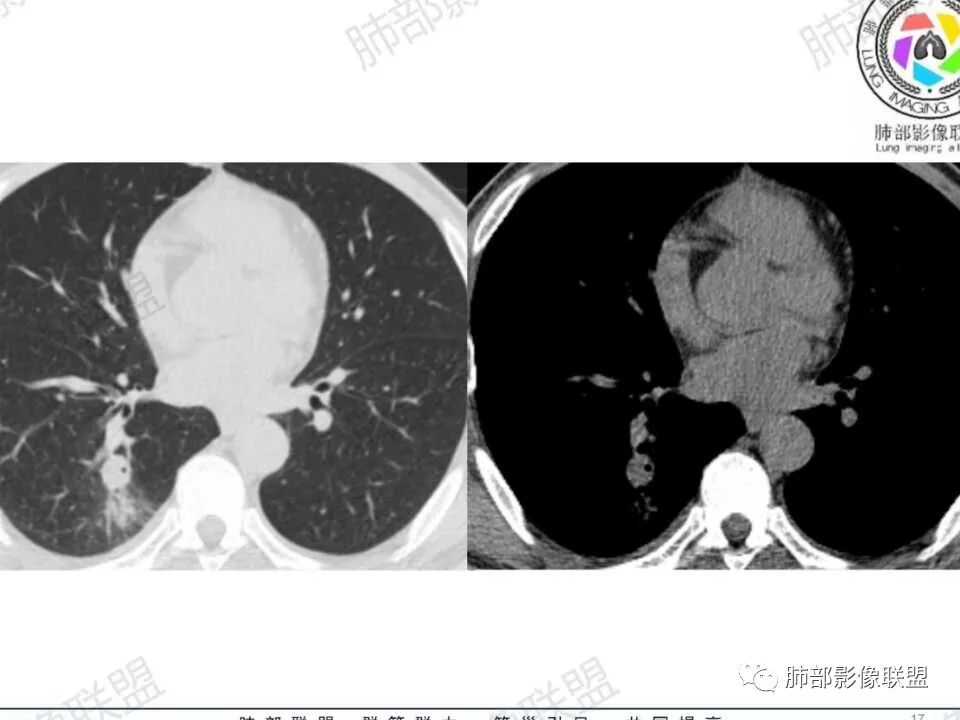

中年男性,糖尿病史,无症状。右肺下叶类圆形结节,边缘光滑,支气管近端阻塞,远端淡片影,树芽还是阻塞性炎症?感觉像树芽,沿支气管分布,无明显强化,治疗一周后复查CT,支气管通而不畅,近端小空洞,远端淡片影加重。考虑肺结核可能性大,鉴别肺癌并阻塞性肺炎。

中年男性,糖尿病史,无症状。右肺下叶类圆形结节,边缘光滑,远端树芽征,沿支气管分布,无明显强化,治疗一周后复查CT,支气管通而不畅,近端小空洞,远端树芽征进展为磨玻璃影。考虑肺结核可能性大。

中年男性患者,有糖尿病基础。右下肺结节较1年前增大,CT表现:右肺下叶后段类圆形结节,边界清楚,边缘部分膀隆、部分平直,内部大部分密度均匀,其中见小条状低密度影(粘液栓?),近端支气管堵塞(抗感染治疗后见大部分通畅,近端支气管进入截断入口圆钝、远端支气管稍扩张),综合考虑结核可能性大,治疗后病灶呈支气管挂果,注意鉴别错构瘤。

复查时支气管似乎通了

腔内似乎有物质堵塞

但是结节内出现含气影

远端楔形,符合阻塞的特点

觉得远端是小树芽